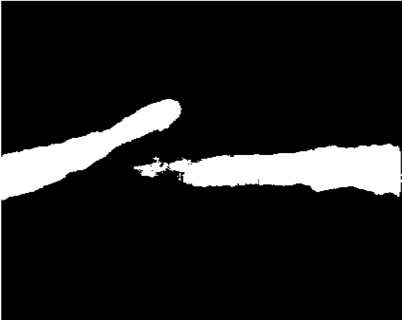

Our challenge was made up of 3 sub-problems. The first was binary instrument segmentation, where each frame was separated into da Vinci Xi instruments and a background class, which contained an ultrasound probe, surgical clips and porcine tissues. The second task was instrument part segmentation, where we scored the participants on whether they could correctly segment each articulating part of the instrument (see Fig. 3). Our final task was to segment and classify the instruments (see Fig. 4).

We provided the first 225 frames of 8 sequences as training data and kept the last 75 frames of those 8 sequences as test data. 2 of the full 300 frame sequences were kept as test sequences. Test labels were kept hidden from the participants. Our datasets contain 7 different robotic surgical instruments. The Large Needle Driver, Prograsp Forceps, Monopolar Curved Scissors, Cadiere Forceps, Bipolar Forceps, Vessel Sealer and additionally a drop-in ultrasound probe, which is typically held in the jaws of the Prograsp Forceps instrument. Samples from the training datasets are depicted in Fig. 2 and examples of the different instrument types are shown in Figure 3 and 4.